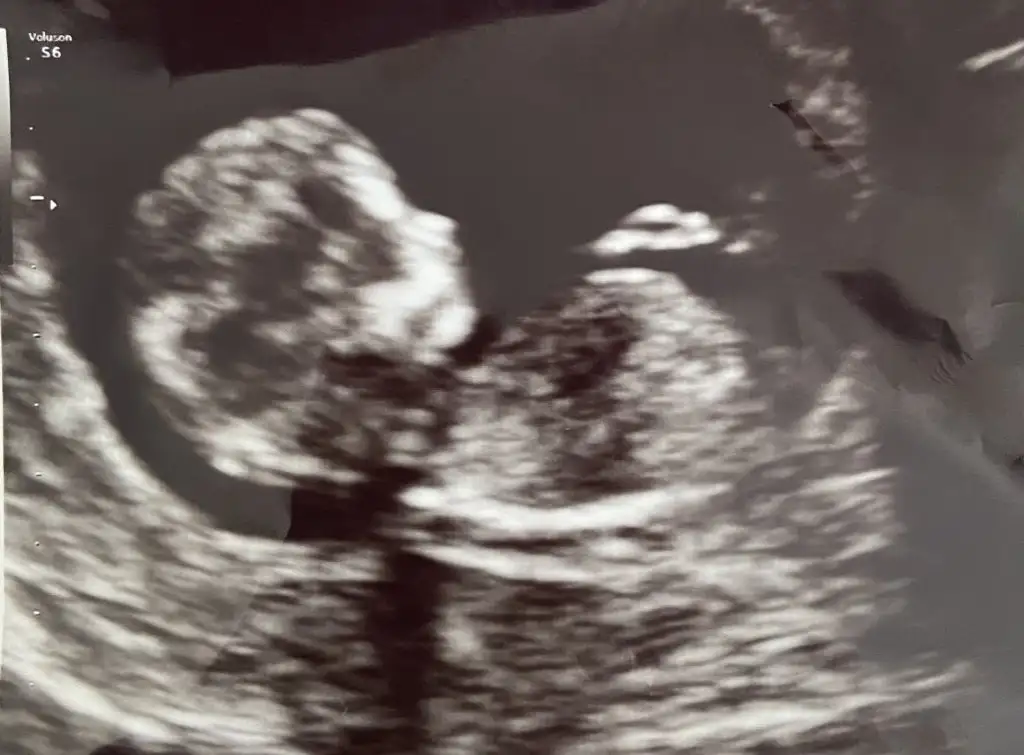

Ultrason ne kadar net çıkmış maşallah benimki çok bulanıkEki Görüntüle 3147933

Ben de cinsiyet bilmiyorum henüz. Ama burada yorum yapanların çoğu erkek dedi. Kıyas yapabilirsinizben de çok anlamıyorum gerçi de. Benim bebeğim de burada 12+2ydi sanırım

En son benimkide çok hareketliydi bi sağa bi sol tarafa dönüyordu kafasıBurda çok netti ama bundan 1 hafta sonra gittiğimde o kadar hareket ediyordu ki net bir şey yakalayamamıştı. Bebeğin duruşu çok önemli

Kizlar 12.hafta ultrasonumuz , cinsiyet erkek kesinleşti, fikir olsunYaa hadı inşallah benim bebisimde erkektir

Kizlar 12.hafta ultrasonumuz , cinsiyet erkek kesinleşti, fikir olsun![]()